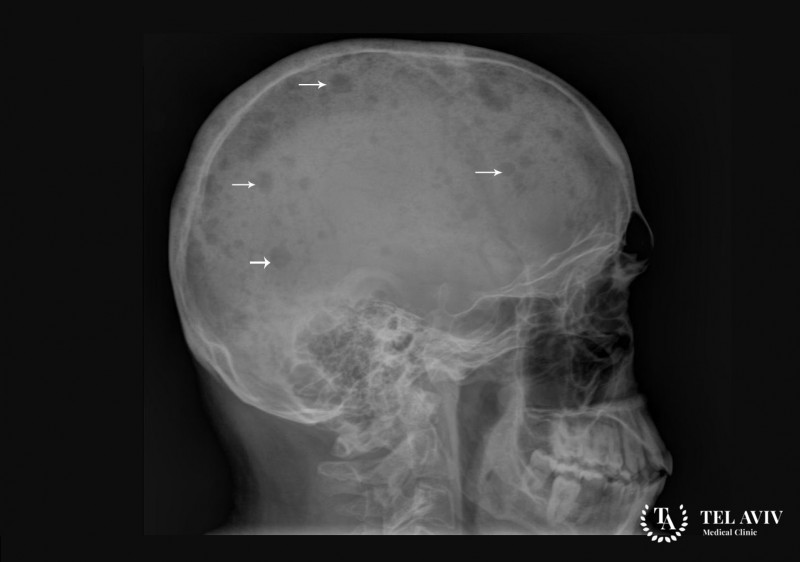

Одним из наследственных видов заболеваний крови является талассемия, обусловленная нарушением синтеза цепей компонентов, входящих в состав гемоглобина. Причиной аномалии называют […]